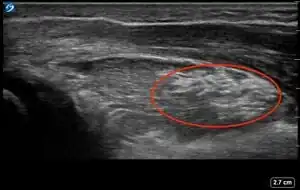

| 3 | Cortical Break Fracture | "Broken" | Break, step or gap in bone cortex which appears as a black zone in the bright, sharp white line[10][11][14][15][16] | ![]() |